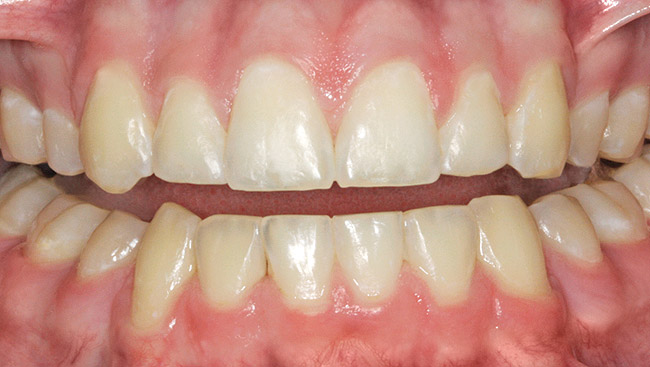

Figure 3  White spot lesions evident after orthodontic therapy (photograph courtesy of S. Paris and H. Meyer-Lueckel).

Figure 3

Figure 4  White spot lesions are imperceptible, blending with natural tooth color, after caries infiltration therapy (photograph courtesy of S. Paris and H. Meyer-Lueckel).

Figure 4

Caries infiltration is indicated for all age groups, up to the first third of dentin (D-1) (Figure 2). It is especially advantageous in interproximal areas, where a relatively large ratio of healthy hard tissue must be removed to eliminate carious tissue. Infiltration replaces hard tissue lost due to demineralization (to a maximum of 800 µm) with a low-viscosity resin, creating a barrier to further diffusion of carbohydrates and organic acids within the hard tissue, not on the tooth surface. This barrier stabilizes and effectively blocks the caries without changing the anatomic shape or appearance of the tooth.85 Additionally, treated lesions lose their whitish opaque color and blend with surrounding natural enamel, which is especially esthetic in the smooth surface type of lesions often found when fixed orthodontic appliances are removed (Figure 3 and Figure 4).